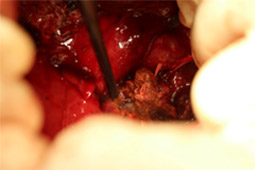

病名:上顎の扁平上皮癌  手術法:左上顎および頬骨切除手術

症例:チワワ 8歳齢 避妊雌

主訴:1ヶ月前から左上顎の第1〜2後臼歯にかけて始めは小さい腫瘤ができていましたが、急激に大きくなり近医を受診されました。そこで上顎の悪性腫瘍を疑うとのことで当院に紹介で来院されました。当病院初診時、腫瘍はすでにかなり大きくなっており、左眼窩の近くおよび頬骨まで浸潤が認められました。

上顎の奥の腫瘍は非常に手術が困難な場所ですが、飼い主様の強い希望により、腫瘍切除手術を行いました。

手術摘出後は2日目から食事可能となり、1週間程で退院としました。腫瘍の病理組織検査では扁平上皮癌との診断でしたが、マージンクリーンで取りきれており、現在術後1年以上経ちますが再発もなく経過良好です。

飼い主様が一時は諦めかけていただけに、無事手術で元気になってほんとに良かったと思いました。